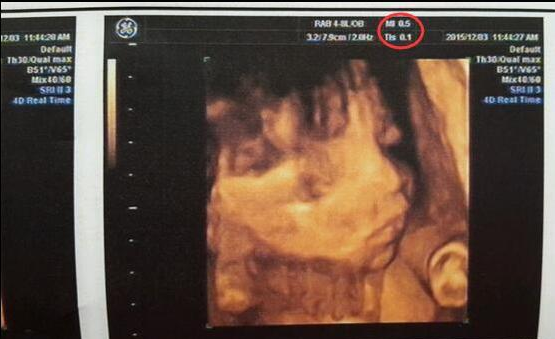

那么这个时候你肯定会问,那究竟怀孕了测生男生女,哪种办法才能准确无误呢?其实,不用我说你也知道,看生男生女,最准确的方法无非就是B超了(普通黑白B超和四维彩超都可以,不过,四维彩超更清晰)。

如果你还不相信,那我告诉你,所谓的M与F只不过是孕期检查时一般的记录缩写罢了。如:头顶先露即为“枕”(缩写为O);臀部先露即为“骶”(缩写为S);面部先露部位即为“颏”(缩写为M);肩部先露即为“肩”(缩写为S)这是B超检测一般记录。

在去网上看看大家对于这种“通过四维彩超单辩男女”真实性的帖子发现,大部分四维彩超单子上面显示的都是MI,FMI是极少数现象。

从四维单子mi和fmi的区别预测怀孕生男生女超准?别傻了,网上这种说法是并不准确的,当然,有部分宝妈生出来的是男宝,而刚好B超单子上又有这个MI,所以将M=Male,但其实这只是一种巧合而已,并不能当做判断宝宝是男宝还是女宝的标准,请各位宝妈们不要盲目迷信这些数据。

再说了,其实我们自己是看不懂单子数据的,别看什么胎心什么的,那个都不准,宝宝健康比什么都重要,四维虽然能看见宝宝的脸,但并不能完全肯定宝宝性别啊,在新时代检查的时候,主要就看看宝宝是否健康,做个大排畸就对了。